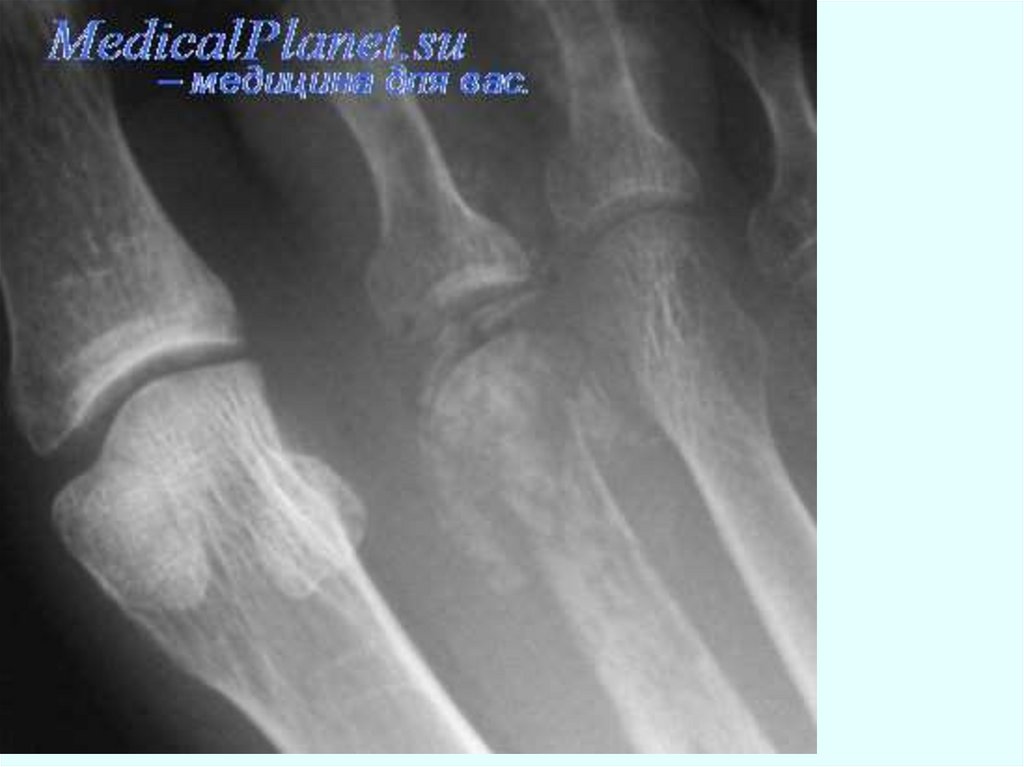

ОСТЕОМИЕЛИТ - гнойное воспаление костного мозга с

вовлечением кости и надкостницы.

Возбудитель – стафилококк, стрептококк, пневмококки,

туберкулезная палочка и т.д.

Инфекций попадает экзогенно – извне через поврежденную

кожу и слизистые оболочки; эндогенно - с током крови.

Различают:

гематогенный;

травматический

контактный остеомиелит.

Острый гематогенный остеомиелит - чаще встречается у детей

и подростков.

Воспалительный процесс локализуется в длинных трубчатых

костях (голень, бедро, плечо).

39.

Диагностика

Анализ крови:

лейкоцитоз со сдвигом формулы влево,

ускоренное СОЭ,

анемия,

уменьшение белка.

В моче:

белок,

лейкоциты,

цилиндры.

R-логические признаки

появляются через 10-14 дней,

утолщение надкостницы,

«размывание»

костной структуры

с последующим образованием полости в кости.

Ранним признаком является уплотнение тени мягких тканей.